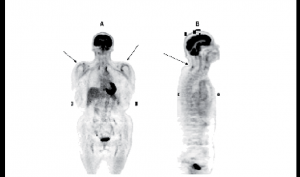

Cas Clinique : Monsieur G., 84 ans, syndrome grippal – Une tricytopénie rapide

Monsieur G., âgé de 84 ans, est autonome à domicile, mais avec une relative incurie. Il ne prend aucun médicament, sauf peut-être du millepertuis. Il a comme antécédent essentiel une…

Cas clinique : Monsieur G., 84 ans, syndrome grippal, une tricytopénie rapide